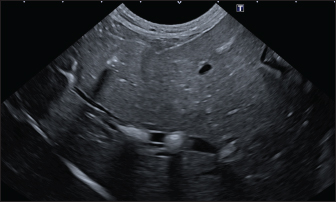

In the aligned pattern, mineralization foci are often millimetric, rarely sub-centimetric, forming isolated linearities in the hepatic parenchyma, without a real branching pattern, seeming to follow the course of some intrahepatic biliary ducts (Fig. 2). Sub-centimetric and centimetric IBTM determined a focal dilatation of the biliary ducts in 34.4% of dogs (11/32). In eight of these subjects (25%), we also found millimetric IBTM randomly distributed in the liver.

Fig. 2. Ultrasound image of the liver showing millimetric IBTM not generating acoustic shadow, with an aligned pattern.